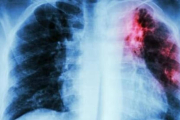

В республике сохраняется неблагополучная ситуация по туберкулёзу Больше всего заболевших - в Слободзейском и Каменском районах, а также Тирасполе 20 Мар., 2024, 11:51 Общество Туберкулёз Заболеваемость

Заболеваемость туберкулезом в Приднестровье продолжает оставаться высокой В Минздраве сообщили, что нашли помещение для принудительного лечения пациентов с этим диагнозом 20 Апр., 2023, 11:08 Общество Туберкулёз Итоги года

В Рыбницком районе за год зафиксирован самый высокий показатель заболеваемости туберкулёзом Всего в Приднестровье в прошлом году заболевание впервые выявили у 253 человек 03 Мар., 2023, 09:45 Общество Минздрав Туберкулёз

Количество заболевших туберкулёзом в Приднестровье ежегодно уменьшается на 5-8% Вместе с тем количество запущенных случаев заболевания растёт 18 Окт., 2022, 10:41 Общество Минздрав Туберкулёз